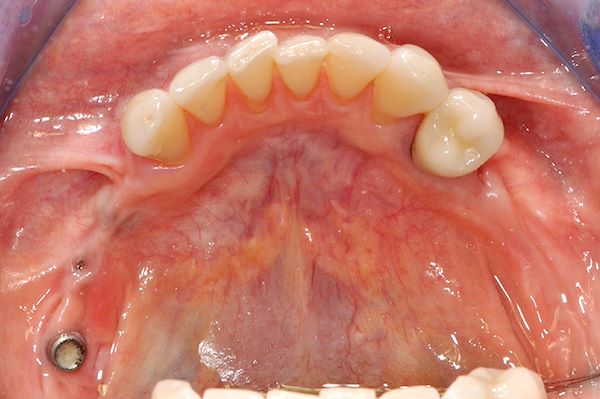

Rimozione impianti integrati e rigenerativa ossea verticale

Visione occlusale arcata mandibolare: si noti la testa degli impianti

Visione occlusale: guarigione avvenuta dopo 3 mesi dalla rimozione degli impianti